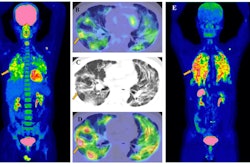

The study included 17 patients who underwent three PET/CT scans of the kidneys and areas where tumors manifest. The patients were intravenously administered an average dose of 5.7 GBq. The researchers also derived lesion and kidney uptakes from PET/CT scans taken one, four, and 20 hours postinjection, respectively.

Lesion uptake from a patient with a solitary fibrous tumor and its FAP expression on gallium-68 (GA-68)-FAPI-46 (A) and intratherpeutic Y-90-FAPI-46 (B). The panel shows the constructed time activity curve with the three PET/CT measurements.SNMMI

Of the total patients, 15 had sarcoma, one had prostate cancer, and one had gastric cancer. The study analyzed 31 primary and metastatic lesions located in the following areas: lung, pancreas, pleura, liver, thyroid, bone, and lymph nodes.